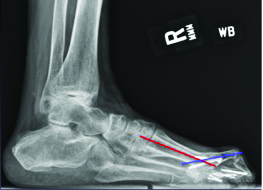

While the technique and use of bone transport can provide success while keeping the first ray out to an appropriate length, one must be mindful of the soft tissue envelope and the lack of intrinsic musculature when performing this procedure. It is also important to base the vector of transport to the distal pins and lengthen parallel to the ground to avoid metatarsus primus equinus. We recommend preserving the metatarsal parabola (approximately 142 degrees with the first metatarsal equal to the third metatarsal). Consider bone transport procedures in two stages on the first metatarsal due to the likely requirement to fuse the distal regenerate bone with the base of the proximal phalanx. In keeping with principles of bone transport and tibialization of the fibula, one can also perform gradual transverse medialization of the second metatarsal and docking with the medial cuneiform and proximal phalanx successfully. Authors have described fibular bone hypertrophy occurring over the course of five years and it is therefore plausible for the second metatarsal to hypertrophy as well.44,45